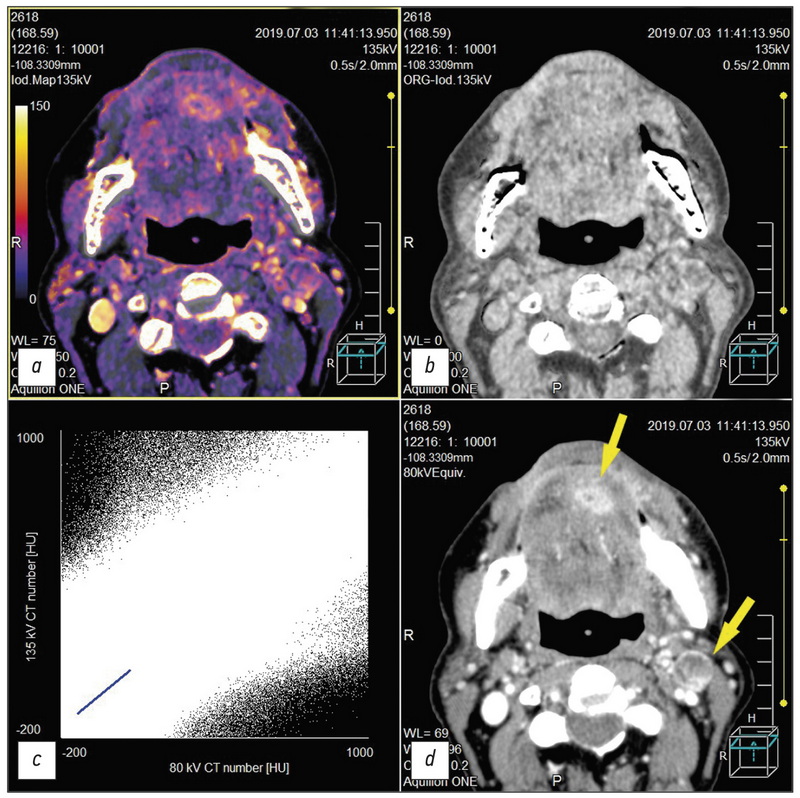

Выполнен обзор публикаций по диагностике рака области головы и шеи методом двухэнергетической компьютерной томографии (ДЭКТ); изучены результаты качественного и количественного анализа данных, полученных методом ДЭКТ с внутривенным контрастированием при опухолях данной локализации; показана важность построения йодных карт для получения дополнительной диагностической информации; описаны аспекты улучшения визуализации орофарингеальной области на фоне артефактов от стоматологических имплантатов. Ряд приведённых в статье научных работ освещает современное состояние вопроса и роль постпроцессинга «сырых данных» ДЭКТ, получения диапазона монохроматических изображений опухолевых и иных патологических изменений области головы и шеи, в том числе сравниваются ДЭКТ с внутривенным контрастированием и рутинная компьютерная томография с точки зрения уменьшения лучевой нагрузки на пациентов, в частности за счёт получения в ходе постобработки виртуальных нативных диагностических изображений из контрастной серии объёмов ДЭКТ. Обзор, помимо последних актуальных научных данных, включает также ссылки на работы по истории развития ДЭКТ как метода. Кратко изложены физические принципы, лежащие в основе ДЭКТ, и перспективы развития метода.